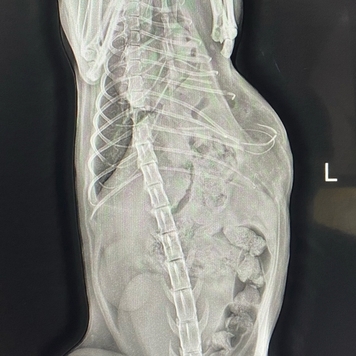

Несчастный случай, травмы и Василиса в Клинике БАРС на приеме неотложной помощи... Проведенная Rg-диагностика показала множественные переломы (один из них - открытый) и значительные внутренние повреждения со смещением органов брюшной полости в грудную клетку. Опытный ветеринарный врач, хирург [club223252442|Анна Сергеевна Кашина] знает, что в таких ситуациях медлить нельзя ни минуты, поэтому она взяла Василису на срочную операцию.

Период восстановления после травматической диафрагмальной грыжи варьируется по времени и зависит от тяжести повреждений внутренних органов, наличия кровотечения и еще ряда факторов. Травмы Василисы были очень серьезными, и, как оказалось в ходе операции, видимые переломы костей - это меньшее из зол. Прогноз был очень осторожным...